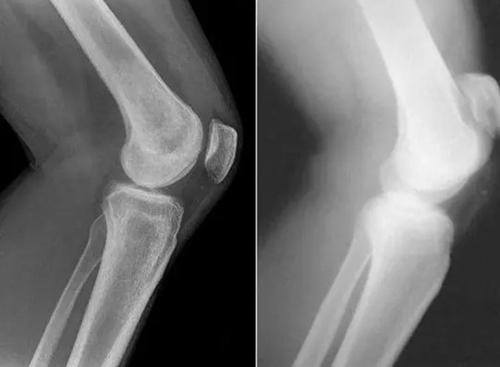

เมื่อเกลือเหล่านี้เกาะอยู่บนพื้นผิวของข้อต่อ คราบเกลือเหล่านี้เหมือนกระดาษทรายที่ทำลายเนื้อเยื่อรอบโดยรอบ กระดูก และกระดูกอ่อน เมื่อผลึกโตขึ้น เกลือจะเริ่มทำลายเนื้อเยื่อของกล้ามเนื้อ เอ็น หลอดเลือด และเส้นเลือดฝอย ทำให้เกิดการอักเสบ ติดเชื้อ บวม ก่อให้เกิดการอักเสบและปวดอย่างรุนแรง

ในกรณีรุนแรง การสะสมเกลือจำนวนมากอาจทำให้กระดูกหักได้ง่ายเมื่อมีการเคลื่อนไหวอย่างกะทันหัน ส่งผลให้พิการและข้อต่อไม่สามารถเคลื่อนไหวได้